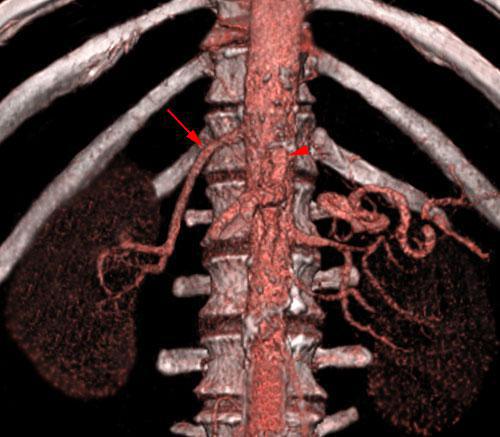

Arterias renales múltiples